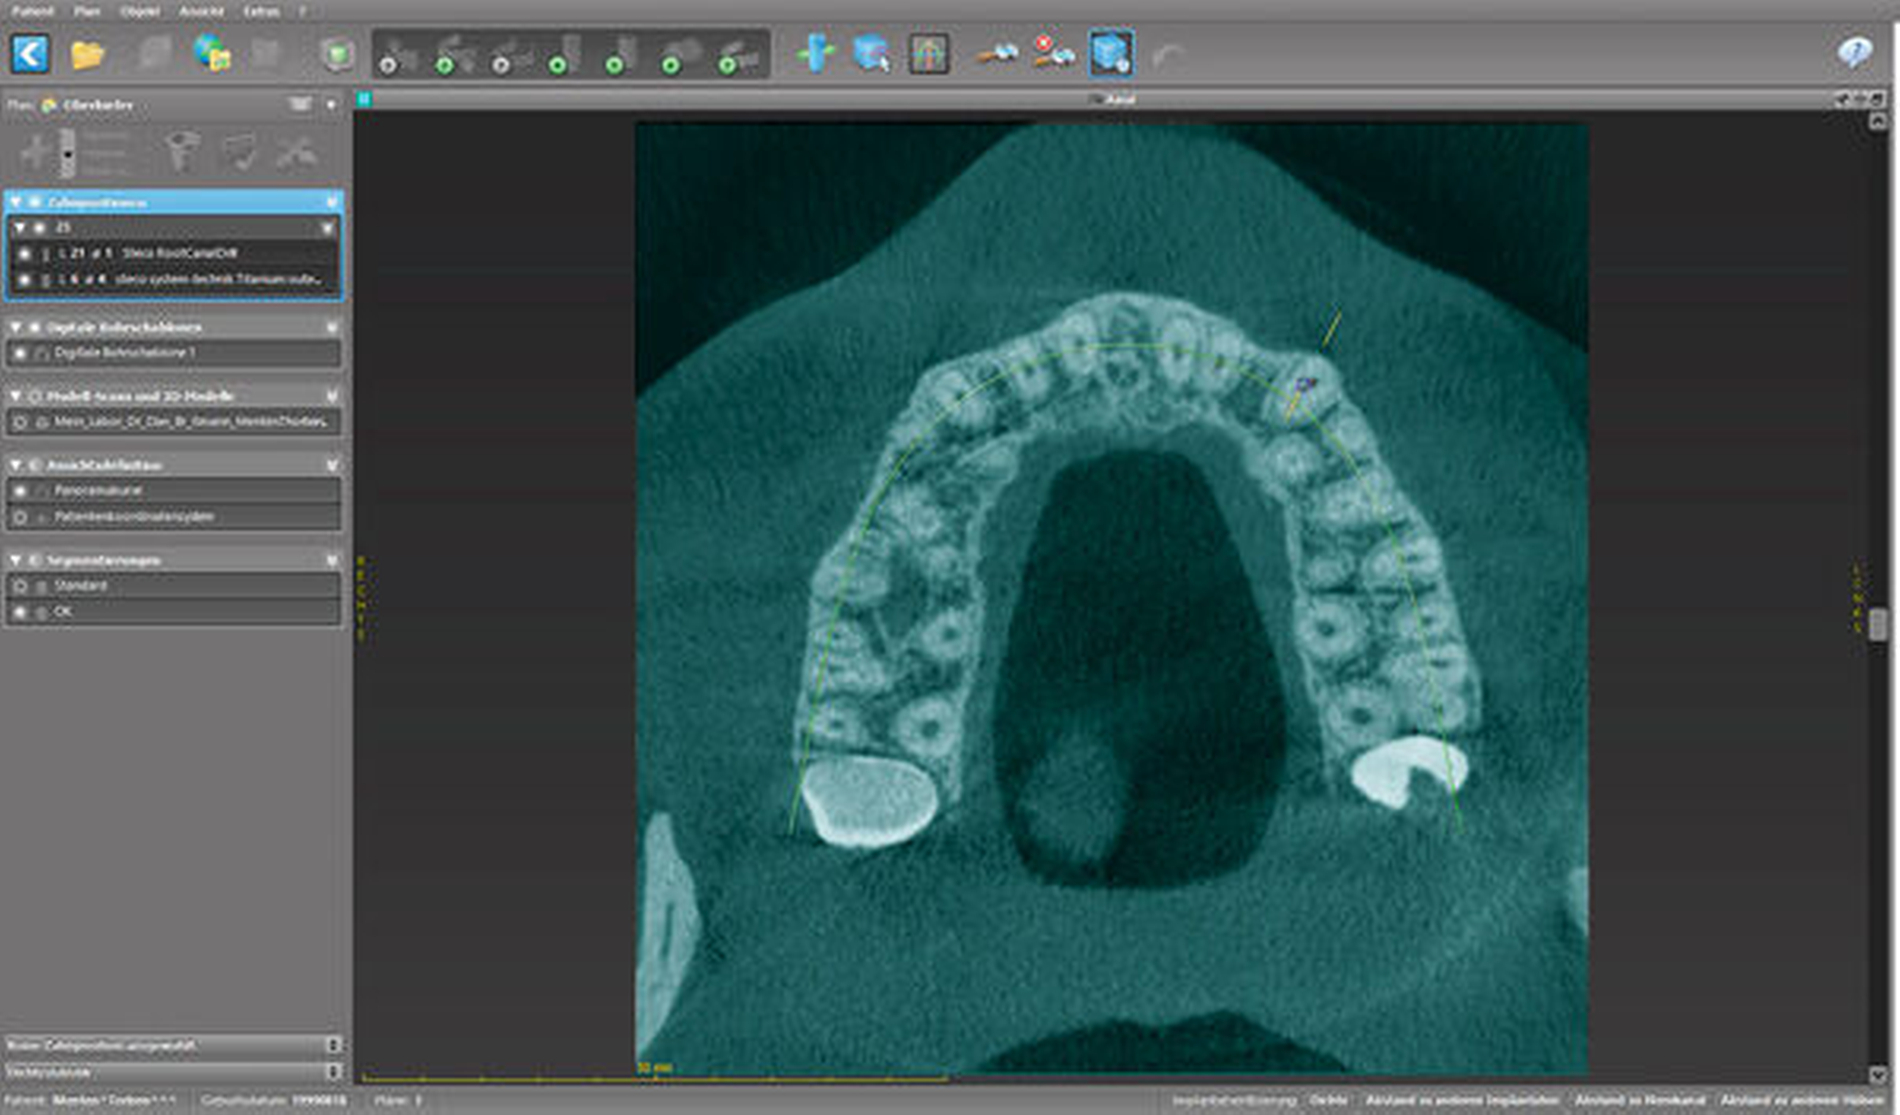

Zunächst wurde hierfür eine DVT–Aufnahme mit einem FOV von 8 cm x 8 cm angefertigt (Orthophos XG 3D, Sirona, Bensheim) und das Oberkiefer-Modell des Patienten gescannt (3Series Dentaler Modellscanner, Dental Wings, Montreal, Kanada). Die DICOM- und SLT-Datensätze wurden anschließend in die Planungssoftware (coDiagnostiX, Dental Wings, Montreal, Kanada) übertragen, fusioniert, und es wurde virtuell eine optimale Zugangskavität geplant. Der verwendete Endoseal-Bohrer (Atec Dental, Ebringen) mit einem Durchmesser von 1,0 mm sowie die auf den Bohrer abgestimmte Endo-Guide-Innenhülse (Steco Systemtechnik, Hamburg) sind in der Software hinterlegt. Bohrer und Hülse werden in der Software so positioniert, dass die Zugangskavität bis in die apikalen Kanalabschnitte erfolgen kann (Abbildungen 5 bis 7). Nach der virtuellen Planung (Abbildung 8) erfolgte die Herstellung der Navigationsschiene mit dem 3-D-Drucker Form 2 (Formlabs, Berlin). Im Anschluss wurde die Hülse in die Schiene eingesetzt (Abbildung 9).